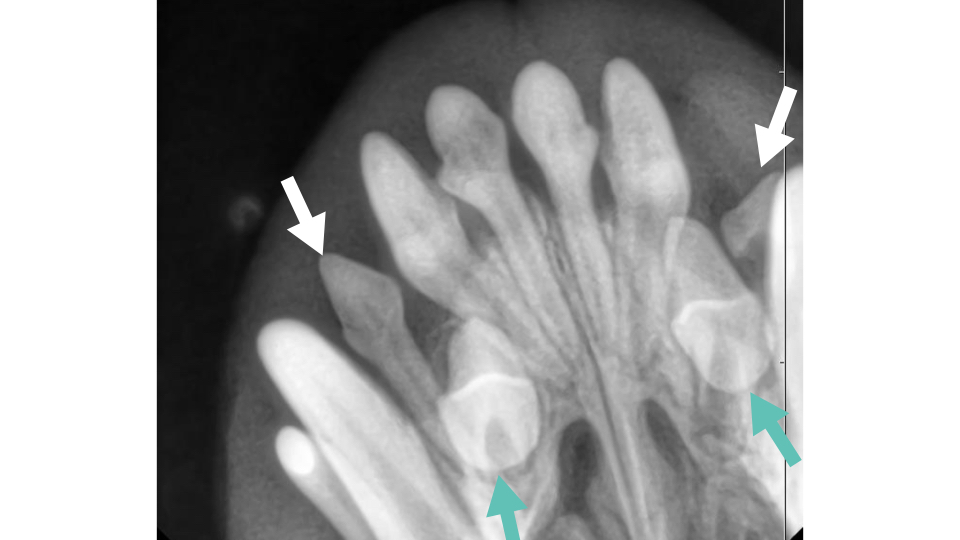

埋伏歯(まいふくし)

- 歯胚は存在するが、歯が萌出せず骨や歯肉内に埋まっている

- レントゲンで歯冠・歯根の像が確認できる

- 放置すると嚢胞(歯原性嚢胞)や骨吸収、歯根吸収などを引き起こすリスクあり

埋伏歯のリスク

埋伏歯は見た目では分からないことが多く、以下のようなリスクがあります。

- 歯原性嚢胞の形成(顎骨を破壊することも)

- 周囲歯の歯根吸収

- 慢性炎症や感染

- 腫瘍様病変との鑑別困難

これらは、発見が遅れると抜歯や顎骨切除など大きな外科処置が必要になることがあります。

埋伏歯が見つかった場合は、嚢胞形成の予防のため早期抜歯が推奨されます。